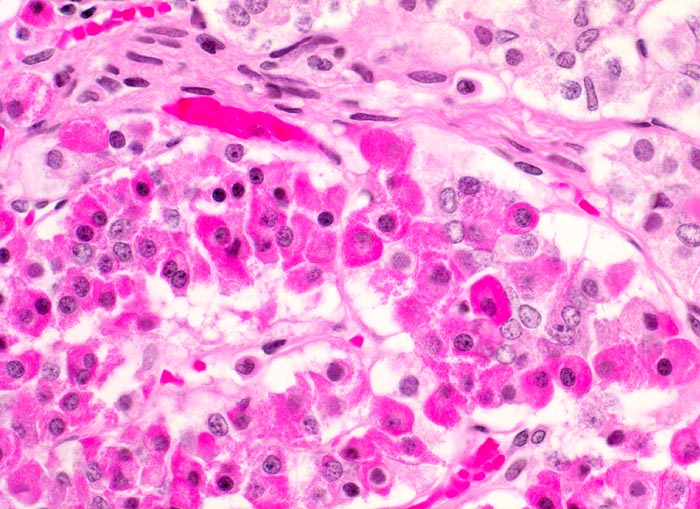

Die Ausstriche sind zellreich und die Zellen sind einzeln, in papillären Verbänden oder Gruppen angeordnet. Zytoplasma ist reichlich vorhanden und ist abhängig vom Typ des Adenoms eosinophil oder basophil. Im Gegensatz zum bunten Zellbild einer normalen Hypophyse wirken die Zellen des Adenoms eher gleichförmig. Die Kerne sind rund und monomorph, das Chromatin ist fein oder Pfeffer und Salz artig. Nukleolen sind meist klein, können aber auch prominent sein. Dignität und funktionelle Eigenschaften sind zytologisch nicht bestimmbar.

Die Differentialdiagnose umfasst Oligodendrogliome und hoch differenzierte Adenokarzinommetastasen.

Unten werden zwei verschiedene Fälle gezeigt.